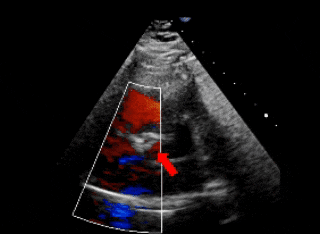

术前超声

左盘展开

保留导丝技术

展开封堵器左盘

超声下可见左盘面贴靠主动脉侧